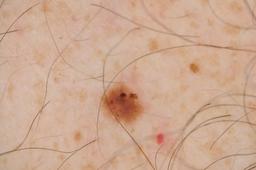

Evaluation set from the ML challenge: SIIM-ISIC Melanoma Classification.